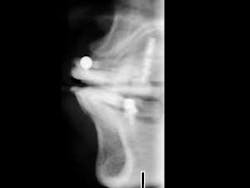

Some practitioners place either type of implant without facial-lingual orientation radiographs which show the quantity and quality of bone. I suggest that radiographs showing the quantity and quality of bone in a facial-lingual orientation should be used for both SDIs and conventional-diameter implants. Such radiographs assist in predicting the ability of the bone to support SDIs.

If the bone is highly trabeculated (porous) in a facial-lingual dimension, SDIs are not indicated. If the bone has dense cortical bone on the facial and lingual aspects of the maxilla or mandible — and lack of density in the center portion — SDIs are usually not indicated. Standard panoramic radiographs cannot demonstrate the needed information. If practitioners use panoramic radiographs only, they may find that the SDIs do not have adequate bone support and they will fail. In my opinion, panoramic radiographs, occasionally periapical radiographs, and some type of facial-lingual radiographs (tomographic, CT scan, or cone beam) are necessary for adequate diagnosis for implants, treatment planning, and surgical placement.

When placing only a few implants, I prefer to use individual, specific-location tomographic radiographs of the proposed implant sites to show the facial-lingual quantity and quality of bone. Such radiographs are desirable even if you are not planning to accomplish the surgery yourself. In my practice, we are currently using a Planmeca panoramic device with a tomographic option (Figure 2). Of course, conventional CAT scans can be used if available in your area. In summary, the collection of diagnostic data is relatively simple and about the same for both SDI- and conventional-diameter implants.